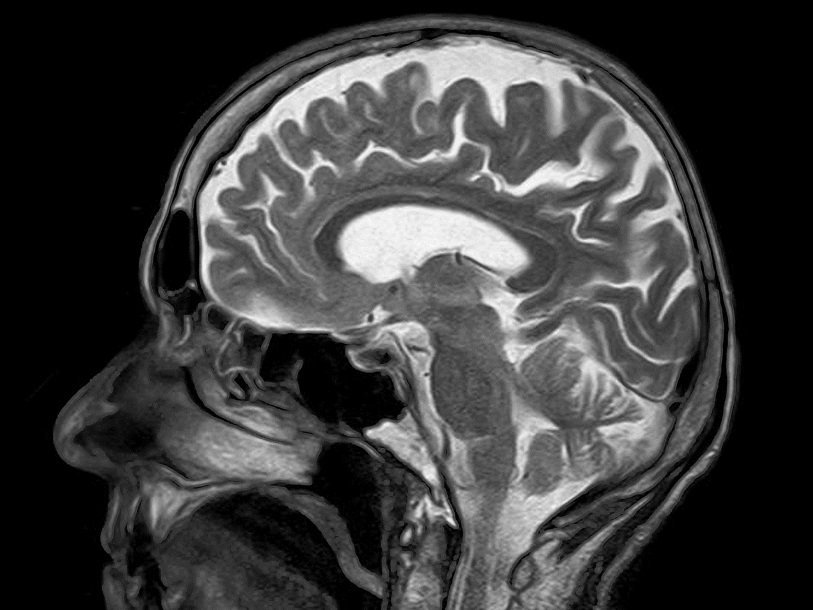

Восстановить нормальную работу мозга этого пациента пытались при помощи электростимуляции блуждающего нерва. В результате он впервые смог следить глазами за объектом и поворачивать голову в ответ на устную просьбу. Его состояние врачи стали оценивать как «минимально сознательное». Подробнее об этом эксперименте и о методе стимуляции блуждающего нерва можно прочитать в очерке «Медленное возвращение сознания».